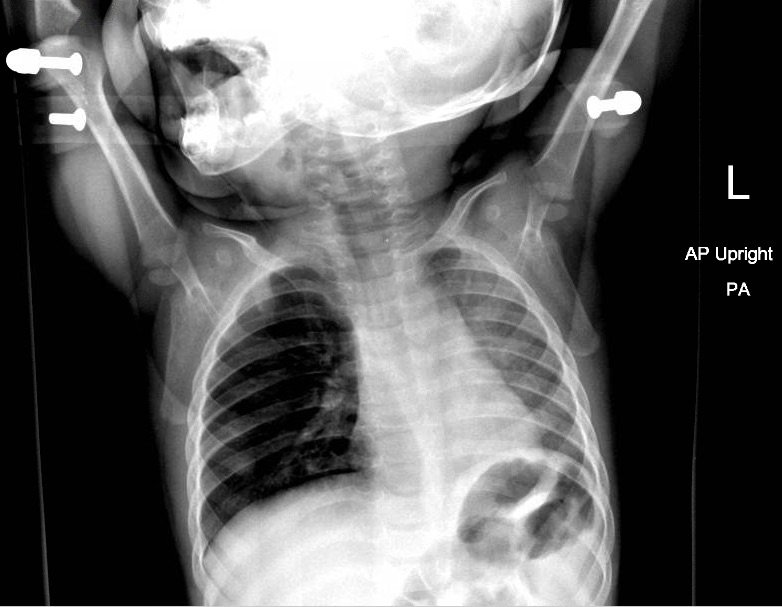

Chest radiograph showed increased radiolucency (red arrow) and flattening of the diaphragm on the right side (blue arrow) consistent with hyperinflation of the right lung, as well as left mediastinal shift (green arrow), indicating obstruction.

Chest radiographs are excellent in detecting radiopaque objects. However, most aspirations are from radiolucent organic matters such as nuts or seeds.3 Radiographs that show focal area of hyperinflation, mediastinal shift, and atelectasis are highly specific for aspiration. Pathological findings on chest radiography showed an 86.1% sensitivity and 63.2% specificity.3 However, it is possible that these finding may not be seen on initial imaging.